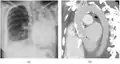

A fibrothorax can typically be diagnosed by taking an appropriate medical history in combination with the use of appropriate imaging techniques such as a plain chest X-ray or CT scan.[3] These imaging techniques can detect fibrothorax and pleural thickening that surround the lungs.[7] The presence of a thickened peel with or without calcification are common features of fibrothorax when imaged.[3] CT scans can more readily differentiate whether pleural thickening is due to extra fat deposition or true pleural thickening than X-rays.[3]

If a fibrothorax is severe, the thickening may restrict the lung on the affected side causing a loss of lung volume.[7] Additionally, the mediastinum may be physically shifted toward the affected side.[3] A reduction in the size of one side of the chest (hemithorax) on an X-ray or CT scan of the chest suggests chronic scarring.[6] Signs of the underlying disease causing the fibrothorax are also occasionally seen on the X-ray.[6] A CT scan may show features similar to those seen on a plain X-ray.[7] Lung function testing typically demonstrates findings consistent with restrictive lung disease.[6]

Extensive left-sided fibrothorax

Chest radiograph displaying inhomogeneous opacification of the left half of the chest that is fibrothorax